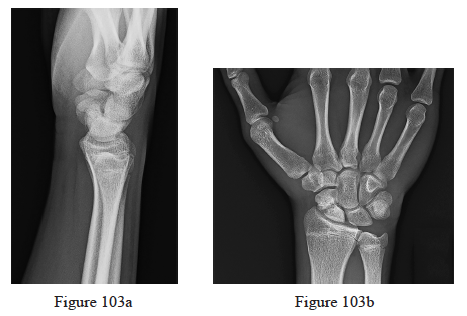

103. Figures 103a through 103d are the radiographs, sagittal-cut CT scan, and coronal T1 MR image of a 16-year-old boy who has wrist stiffness and pain after sustaining an injury 2 years ago. There is no bleeding from the proximal pole during surgery. Which procedure will most likely result in restoration of alignment and healing?